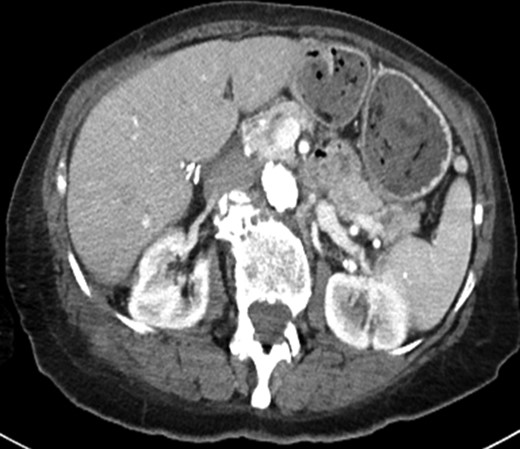

Clinical evaluation of her flank soft tissue tumor demonstrated a tender, non-erythematous, non-fluctuant 7 × 5 cm mass. Biochemical testing, including white blood cell count, was within normal limits. Computed tomography (Fig. 1a) demonstrated a 9.0 × 3.6 cm soft tissue mass and a 6.2 × 3.2 cm fluid collection abutting the right hepatic lobe and right kidney and extending into the abdominal wall. The CT findings were non specific, but the presence of a solid component with enhancing nodularity was suspicious for a neoplasm.

(a) Axial image of the CT of the abdomen with IV contrast, demonstrating a complex partially cystic, partially solid enhancing mass abutting the right hepatic lobe and right kidney and extending into the abdominal wall. (b) Axial T2-weighted sequence of the abdomen (axial T2 Single Shot Fast Spin Echo) showing the cystic component of the mass involving the right retroperitoneal space. (c) Axial T1-weighted fat saturation post-contrast sequence of the abdomen (axial T1 Liver Acquisition with Volume Acquisition after the intravenous administration of gadolinium) demonstrating enhancement of the solid component of the mass extending to the right flank musculature. (d) PET/CT showing increased FDG activity at the solid component identified on CT and MRI within the right flank musculature.